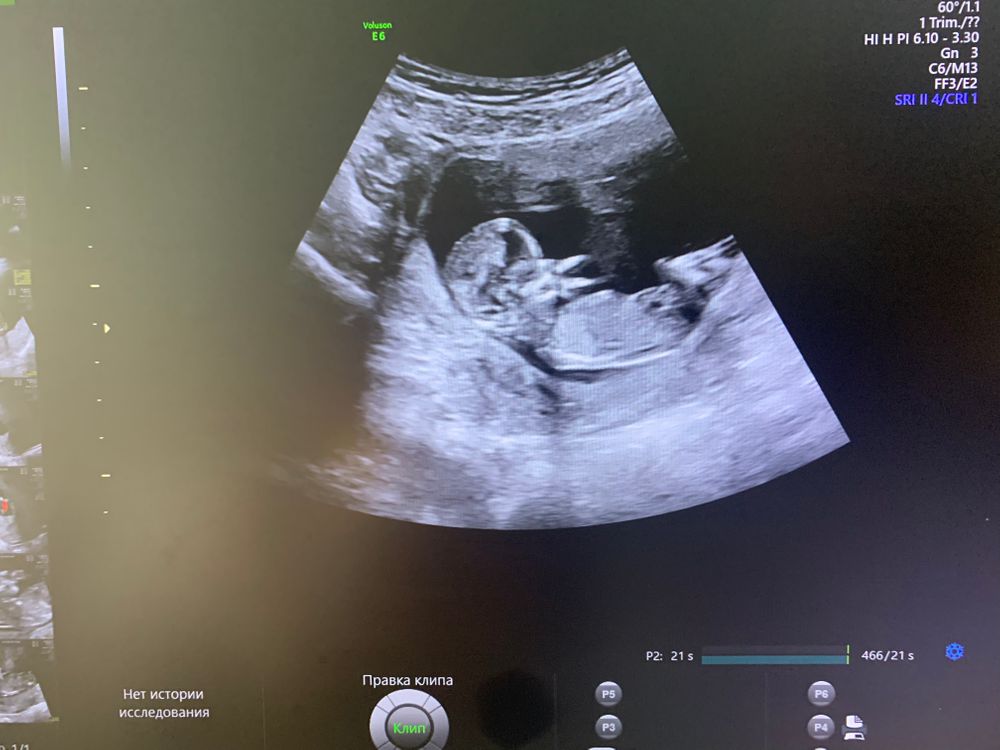

Мальчик будет у вас ❤

Марина, Я фото тётё показала , она узисткой работает лет 20+ уже, сразу сказала мальчуган будет

Марина, ну, правда, пол здесь не видно. Ракурс немного бы правее сместить, чтобы половой бугорок виден был 😊 Некоторые здесь как-то по форме головы определяют, но, по-моему, это не показатель.

Марина, недель в 15-16 уже точно видно будет.

Тонус или связки тянутся? Первый скрининг